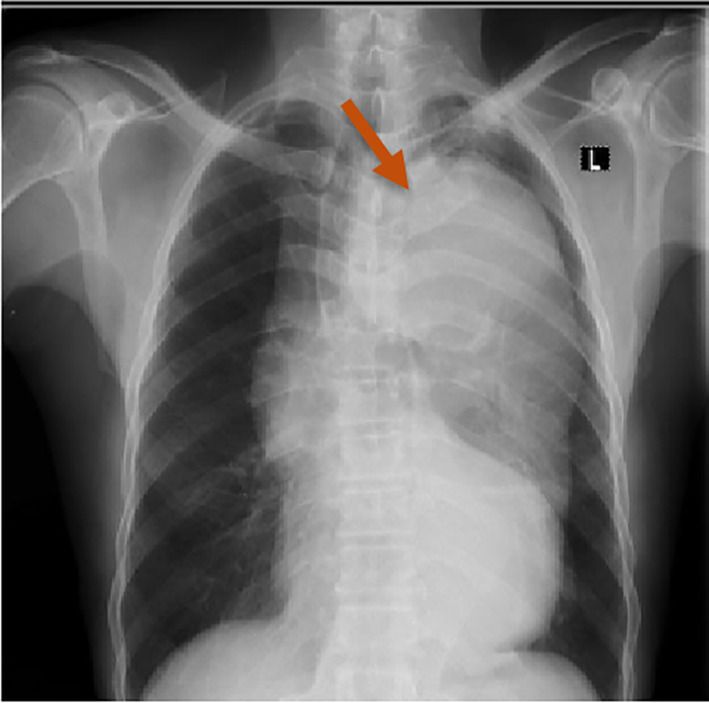

A chest x‐ray revealed a widened mediastinum with a left‐sided soft tissue mass that had displaced the trachea to the contralateral side, which heightened suspicion of an aortic dissection (Figure 1).

Chest radiograph showing widened mediastinum and prominent aortic shadowing.